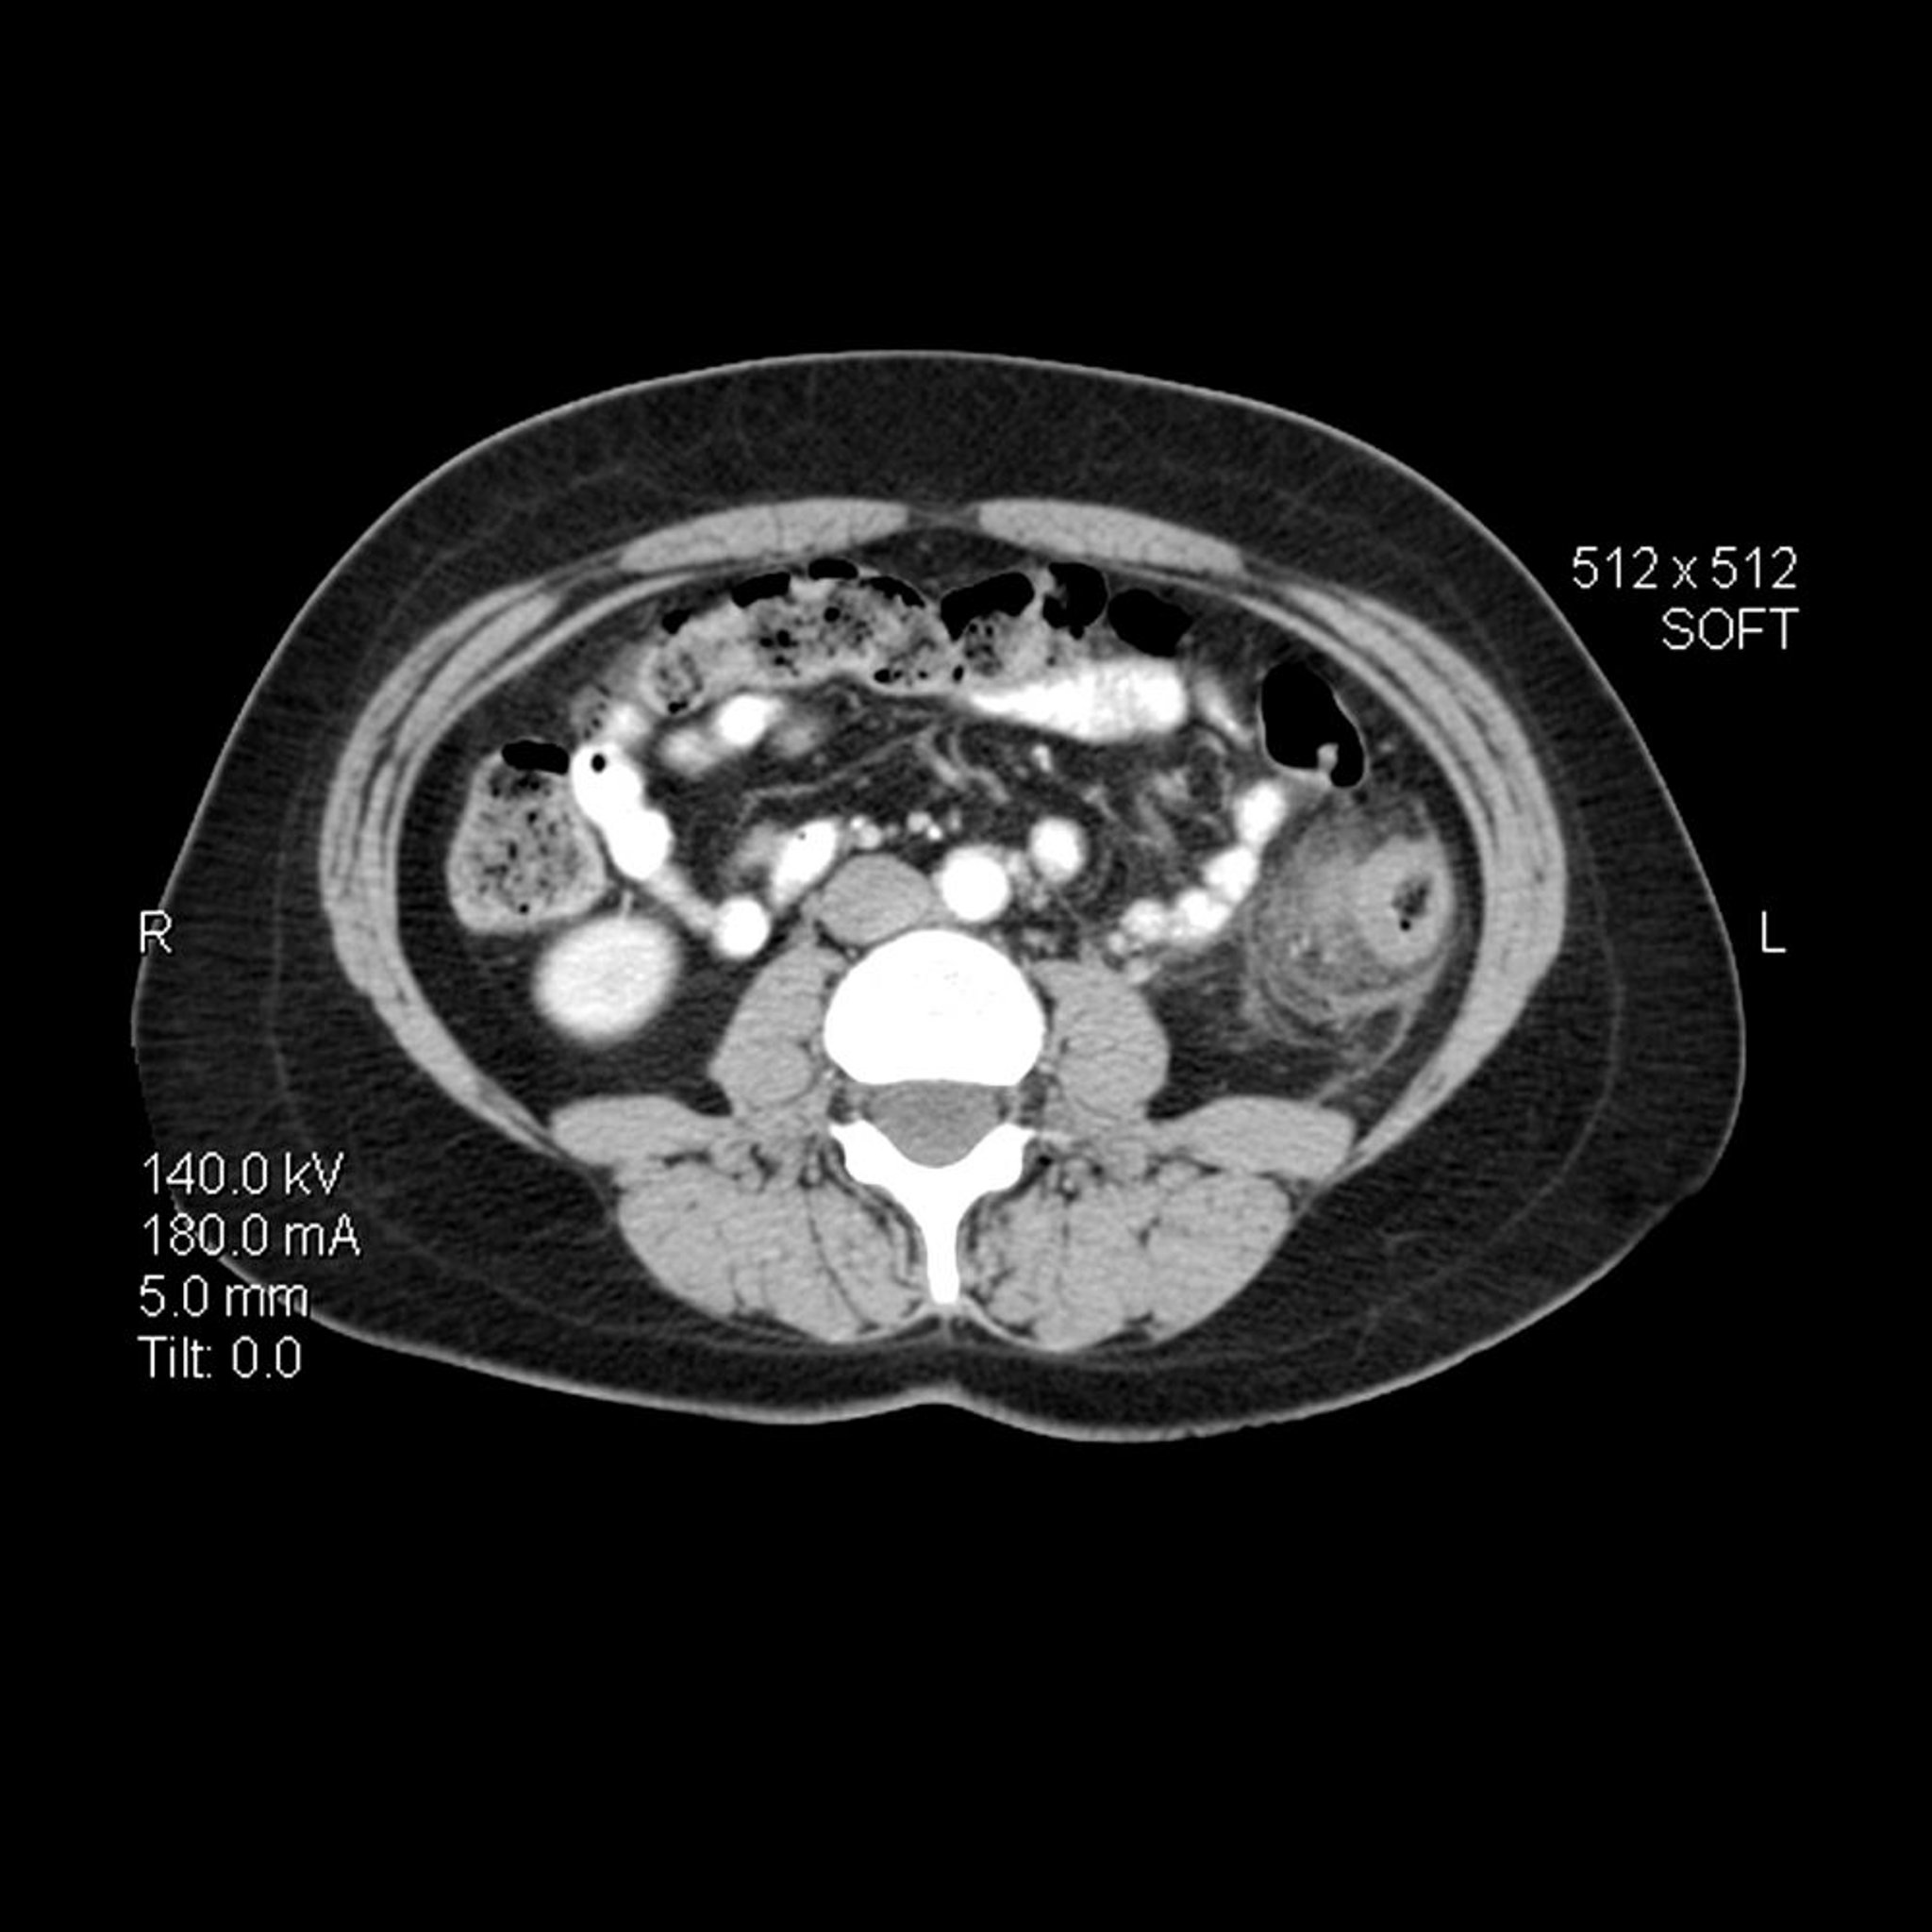

Diverticulite (TDM)

Dans cette image TDM axiale (en coupe transversale) de l'abdomen chez une personne atteinte de diverticulite, la paroi du côlon descendant est épaissie. Il existe également des stries inflammatoires avec une augmentation de la densité de la graisse péricolique adjacente.